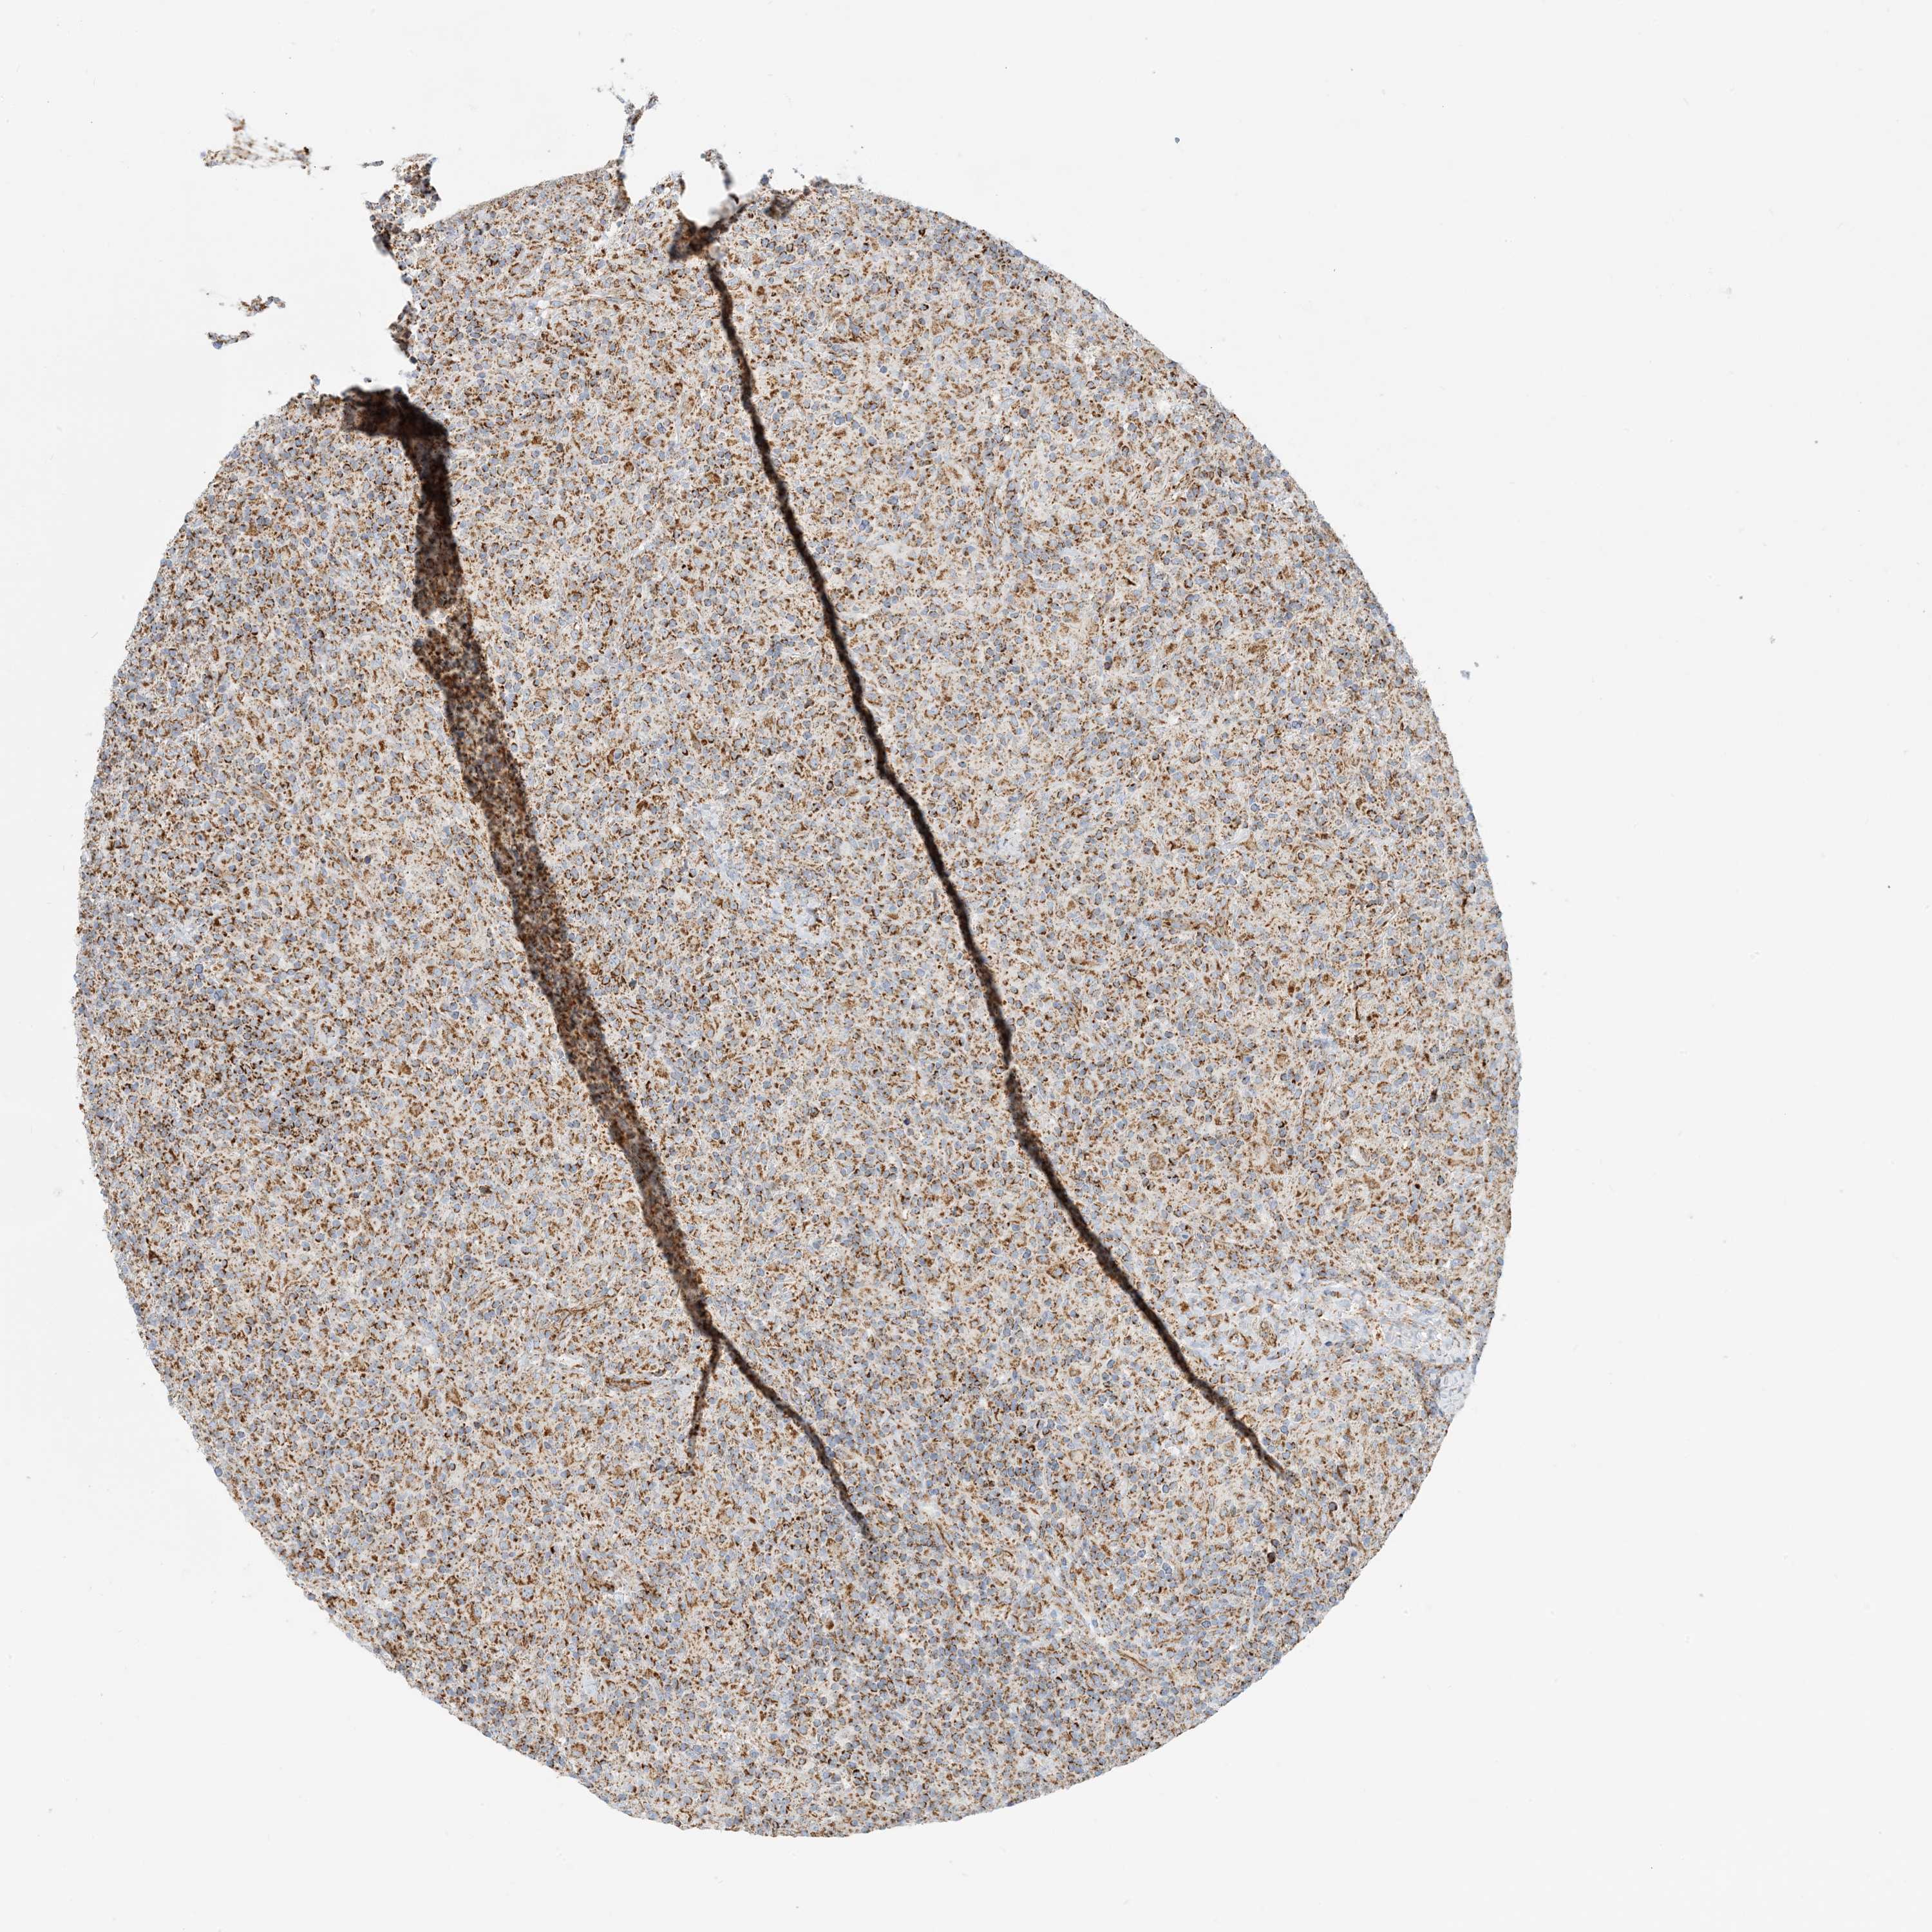

LYMPHOMA - Protein expressioni

A mouse-over function shows sample information and annotation data. Click on an image to view it in a full screen mode. Samples can be filtered based on level of antibody staining by selecting one or several of the following categories: high, medium, low and not detected. The assay and annotation is described here.

Each image is clickable and will lead to virtual microscopy that enables deeper exploration of all samples and also displays staining intensity scores, fraction scores and subcellular localization as well as patient and tissue information for each sample.

Antibody HPA031966

Staining

High

Intensity

Strong

Quantity

>75%

Location

Nuclear

Hodgkin's disease, NOS

Malignant lymphoma, non-Hodgkin's type, High grade

Malignant lymphoma, non-Hodgkin's type, Low grade